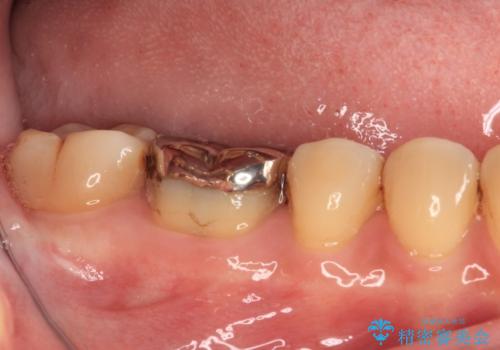

- 人と話す際に、下顎の奥にある銀歯が目立って気になるとのことで来院された患者様です。

左右の奥歯に銀歯のクラウンが装着されていたため、銀歯除去後に仮歯に置き換え、フルジルコニアクラウンにて補綴治療を行うこととしました。